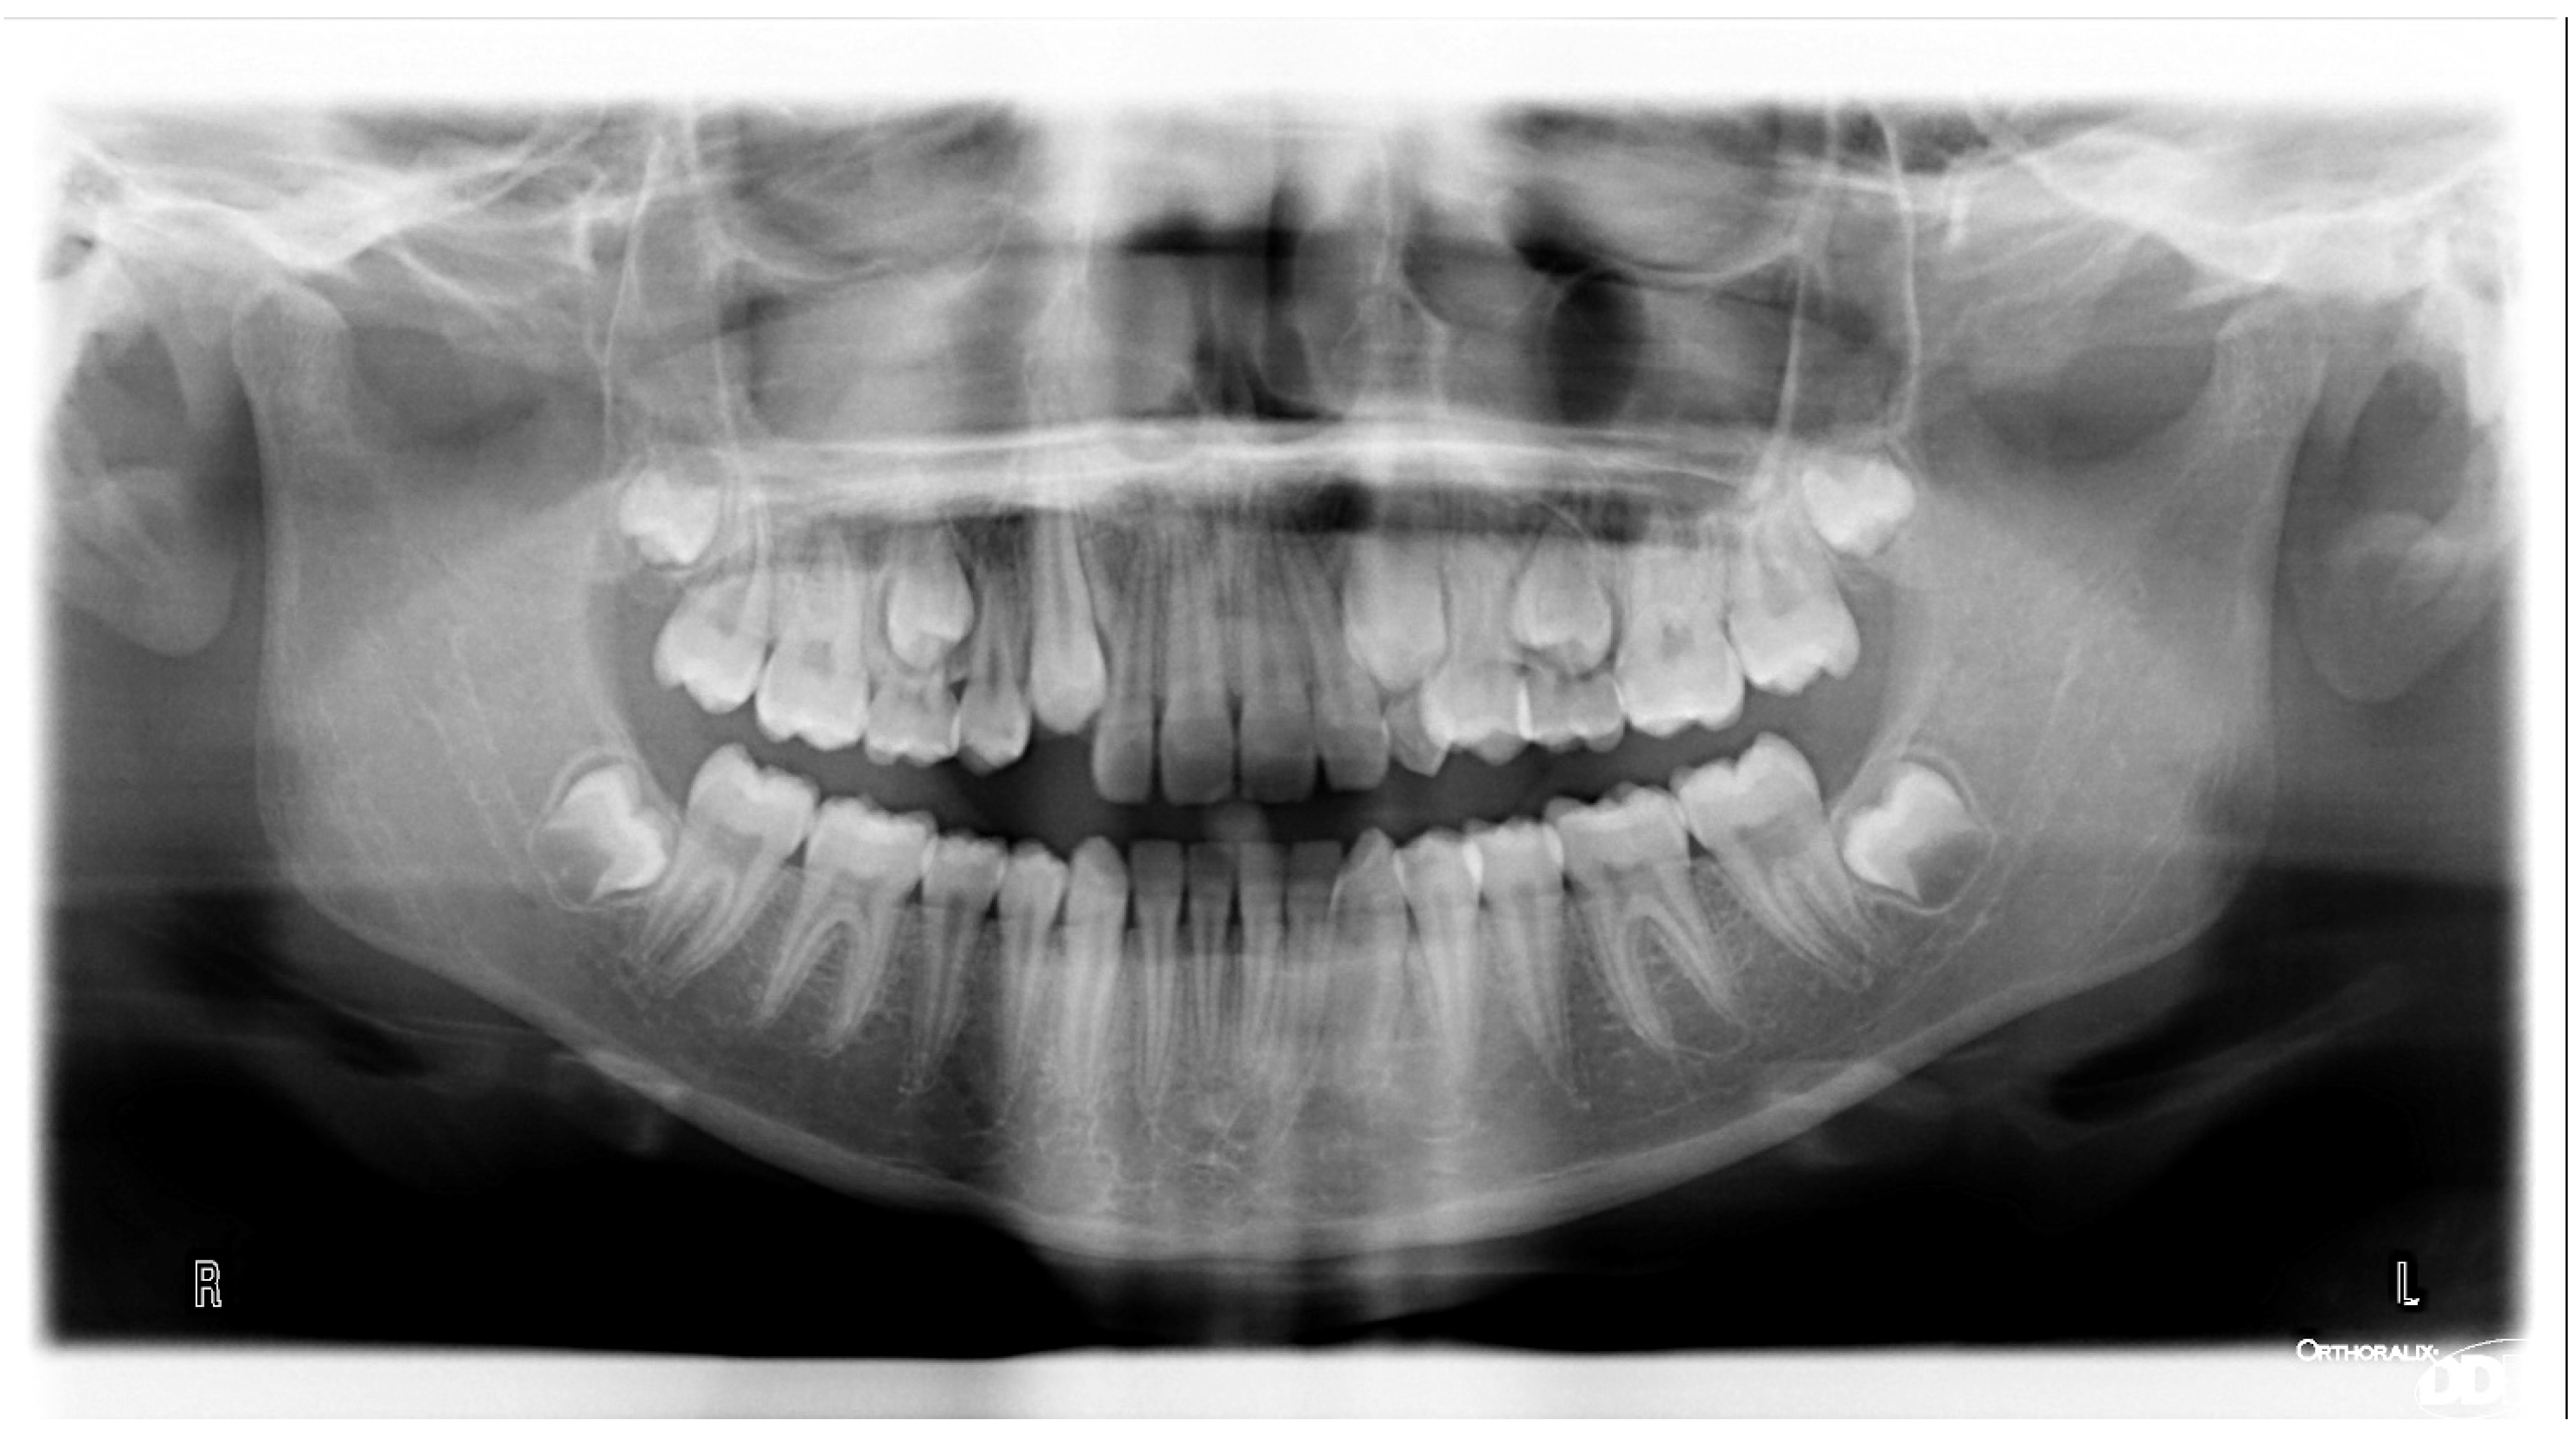

3.1. Clinical Case #1

3.2. Clinical Case #2

3.3. Clinical Case #3

3.4. Clinical Case #4